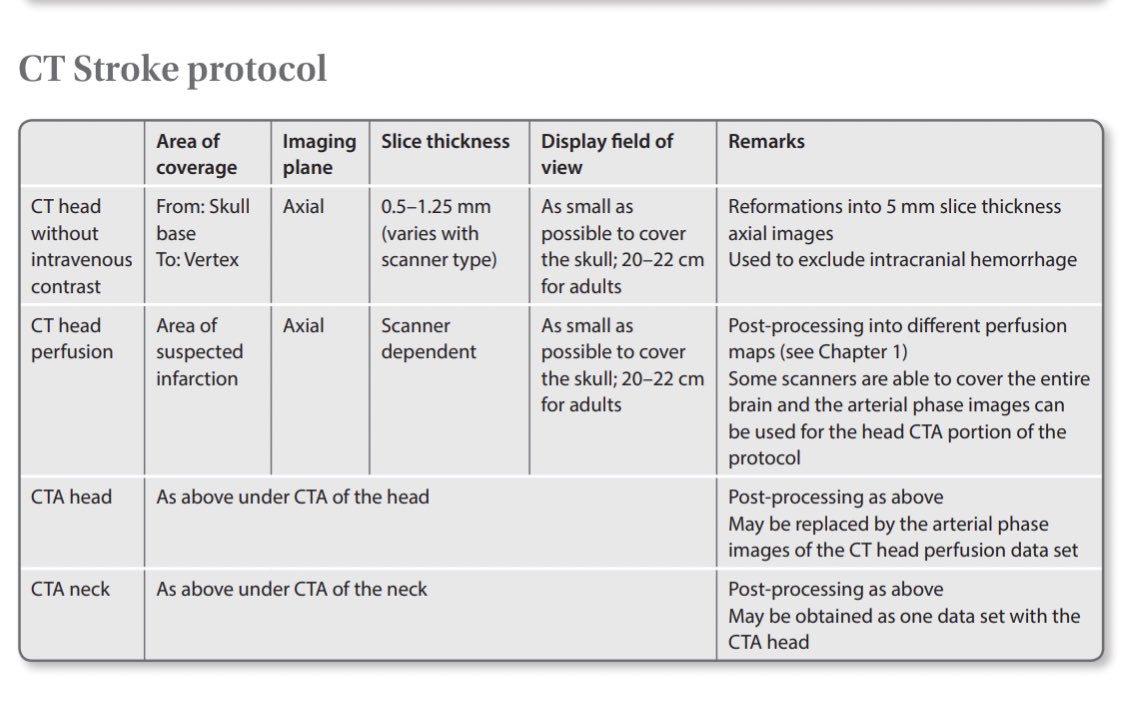

#radiologist #radiologytech

#neurology #ctscan_protocol

-Clinical and radiological features of the stroke syndromes.

-Comparison between different intracranial haemorrhages.

-CT Stroke protocol.

-Time lapse appearence of stroke on CT.

English